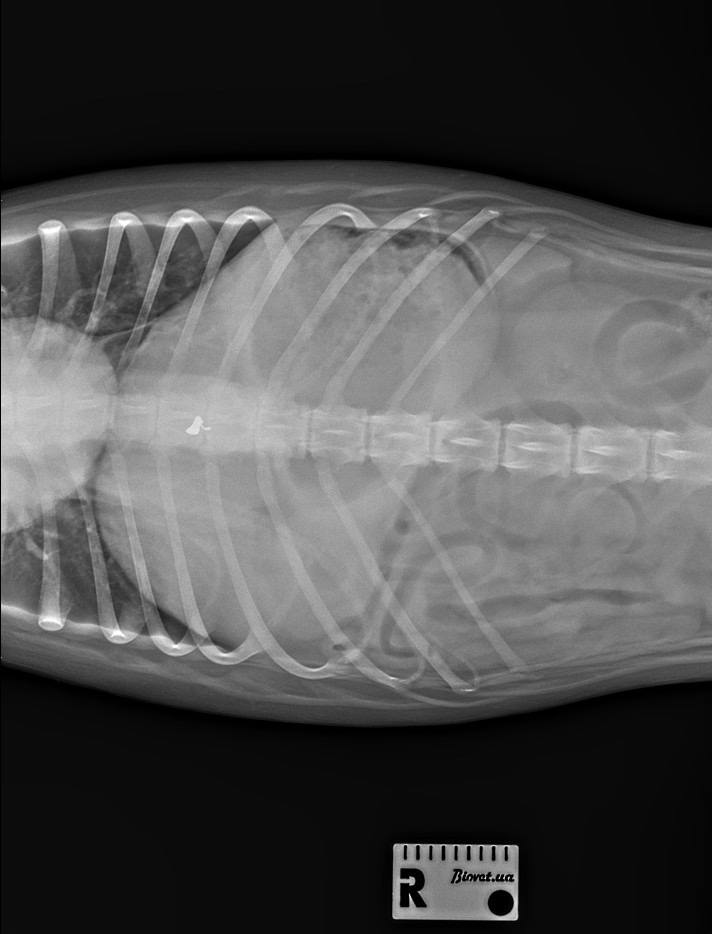

Зауважено, що волонтери у суботу, 21 лютого, звернулися до поліції із заявою на стрілка, проте їм відмовили у відкритті кримінального провадження, адже правоохоронці не побачили на рентгенівських знімках підтверджену ветеринаром кулю від пневматичної зброї.

Варто відзначити, що долею постраждалої собаки почав опікуватися ізмаїльський зооволонтер Роман Таранухін. У неділю Роману вдалося зловити злякану тварину та привезти її до ветеринарної клініки в Ізмаїл. Тут собачку оглянули, зробили рентгенівські знімки. Сьогодні зооволонтер надав «БІ» результати огляду, де чітко зазначено, що рентгенографія у собаки виявила стороннє тіло в спинномозковому каналі на рівні Т9, тому потрібно провести операцію для видалення кулі. Поки тварина не може рухати задніми лапами, а це, скоріш за все, залишить її на все життя інвалідом.

«Сьогодні цю кулю повинні дістати зі спини собаки. Я обов’язково її сфотографую», – пообіцяв Роман Таранухін.